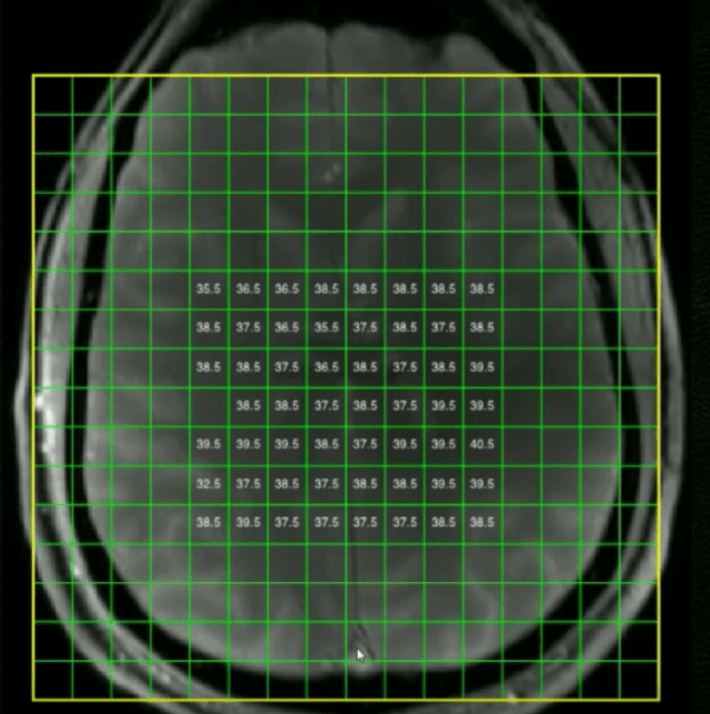

ME-patienter har i genomsnitt 38 graders feber i hjärnan

Som ni ser på ovan bild har ME-patienter i snitt 38 grader i hjärnan och frisk kontrollgrupp 37.5 grader. Förhöjd temperatur i hjärnan indikerar inflammation som kan leda till både utmattning och smärta i hela kroppen.